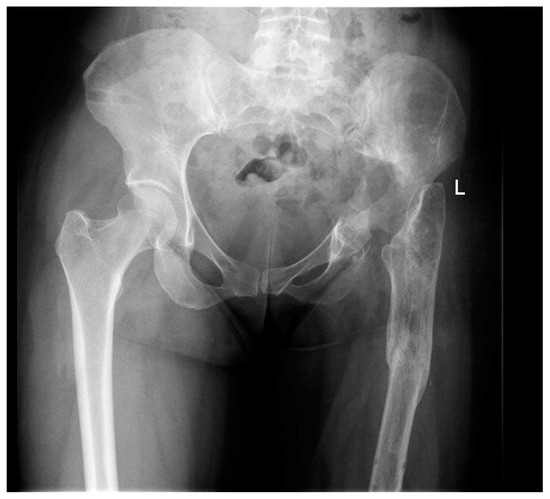

2.1. Case #1

2.2. Case #2